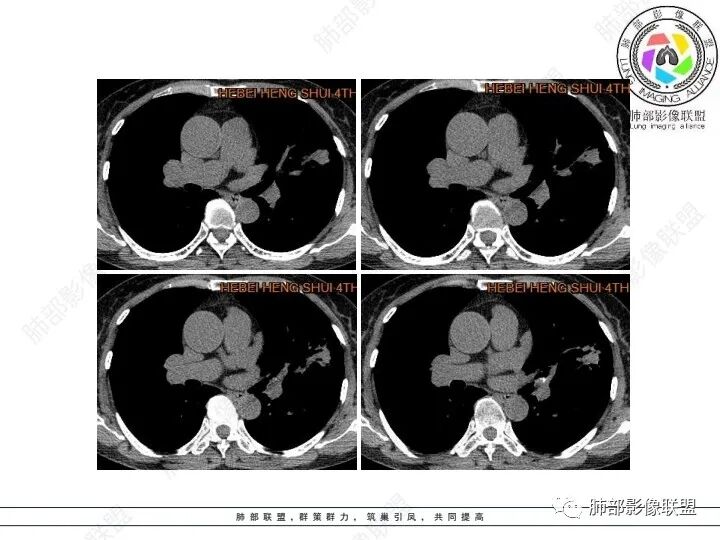

1、临床特点:61岁女性,体检发现肺结节。

2、影像特点:左肺上叶不规则病灶,冠状位、矢状位、斜状位重建显示病 灶整体沿着支气管方向呈斑片状,多结节堆积感明显,病灶大部分边缘显示平直,局部边缘稍膨隆,边界显示比较清楚,近端支气管壁显示增厚,周围可见长索条影及多发结节影,未显示典型“树芽征”。邻近叶间裂未受牵拉凹陷。纵隔窗显示病灶中央可见点状高密度钙化影。

3、病例小结:老年女性体检发现肺部结节,缺乏临床表现,需要警惕恶性。结合影像特点,左肺上叶病灶整体缺乏膨隆感,边缘大多平直,周围多发卫星灶(可见多发长索条影、并非肺CA的细短毛刺),病灶收缩力很弱(邻近叶间裂未见明显凹陷),观察1mm重建图亦可以发现病灶周围没有边界清楚的GGO,病灶内可见钙化点,肺门纵隔未见肿大淋巴结。综合以上,此病灶首先考虑炎性,结核可能性大,有条件可以增强扫描,有助于我们进一步判断。